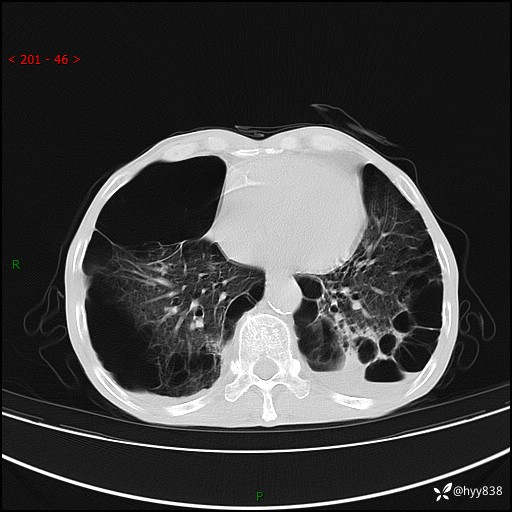

胸部CT平扫+增强